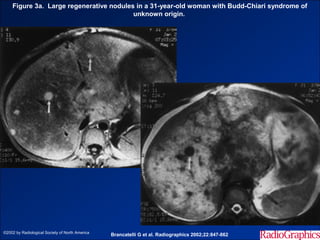

Figure 3a. Large regenerative nodules in a 31-year-old woman with Budd-Chiari syndrome of

unknown origin.

©2002 by Radiological Society of North America

Brancatelli G et al. Radiographics 2002;22:847-862